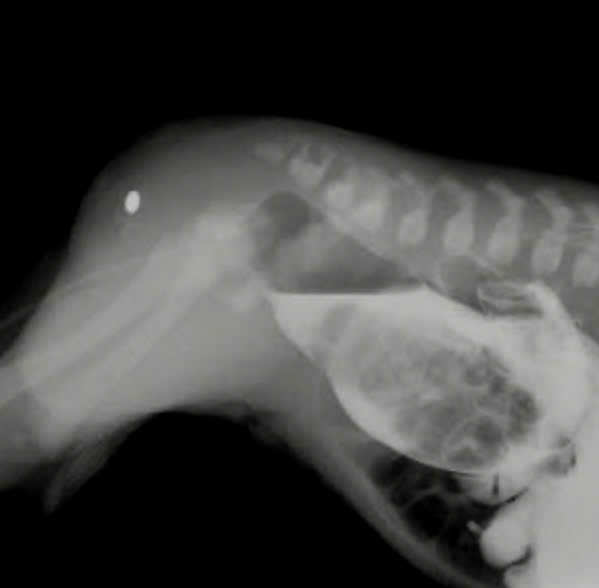

Bé L.T.A.M. (sinh đủ tháng, nặng 3kg) được đưa đến Bệnh viện Đa khoa Khánh Hòa trong tình trạng không lỗ hậu môn, chỉ có một chấm phân su nhỏ ở gốc bìu. Với kinh nghiệm chuyên môn, các bác sĩ tiên lượng đây là ca dị tật phức tạp, chỉ định chụp đường dò trực tràng. Kết quả đúng như nhận định, bệnh nhi bị dị tật hậu môn thể cao, có đường dò trực tràng – bìu – một thể bệnh hiếm gặp, y văn thế giới chỉ ghi nhận vài trường hợp.

Sau khi hội chẩn chuyên môn cùng Bệnh viện Nhi Đồng TP. Hồ Chí Minh, ê-kíp phẫu thuật gồm BSCKII. Nguyễn Thanh Tồn – Phó Giám đốc Bệnh viện và BSCKI. Nguyễn Minh Đức – Khoa Ngoại Tổng quát đã quyết định can thiệp đặt hậu môn nhân tạo tạm thời đoạn giao đại tràng trái và sigma. Khi bệnh nhi được 3 tháng tuổi, ê-kíp tiếp tục phẫu thuật tạo hình hậu môn ngã dọc trước. Trong khi mổ, phẫu thuật viên phải dùng kính vi phẫu để bóc tách đường dò đi sát niệu đạo – một thao tác cực kỳ khó, đòi hỏi độ chính xác cao.